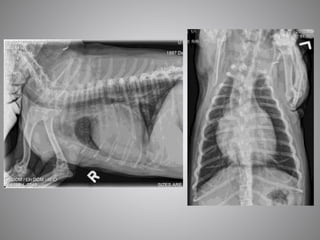

• #15 All these previously discussed changes – stim of SNS, stim of RAAS and fluid retention only occur with SEVERE heart disease. The heart does not fail with mild or moderate changes. Thus animals with MMVD or HCM must have a severely enlarged LA to be in HF. The only exception to this is acute chordal rupture in MMVD in which case there will be severe respiratory signs and a suddenly loud murmur. In DCM there should be severe systolic dysfunction (CHF not likely if FS > 15%) Anything less severe than this, and the dog or cats signs are unlikely due to CHF and other causes of clinical signs should be sort. Thus, sometimes diagnosing CHF can be more difficult than one would think. 1st image – cat with respiratory signs, alveolar pattern, HCM with severe LAE 2nd Doberman with DCM, cough, increased respiratory rate. Severe systolic dysfunction and marked LAE and LVE

• #22 This is one of the most extreme examples of left atrial enlargement without CHF that I have seen. This was a older small breed dog whom presented with chronic cough Despite the extreme LA enlargement, the lung fields are completely clear and the pulmonary veins are small indicating that this dog is not in heart failure. Hence, frusemide is not warranted in this patient. This dog was part of a study I performed during my cardiology training looking at dogs like this. Those that had a heart murmur due to MMVD and a chronic cough but weren’t in CHF. If we look closely at this this radiograph, we can see collapse of the mainstem bronchi on the lateral view and severe collapse of the left lower airways on the DV

• #25 This was on the of the control dogs in the study Small breed dog, chronic cough While the heart looks big on radiographs, he only had mild LA enlargement on echo (LA:Ao 1.5) The reasons of the heart to look big are Shallow chest Expiratory film Both of these instances will result in a smaller volume chest on radiographs and, in relation, make the heart look bigger This dog was not in heart failure. He had a chronic cough and was treated with a combination of doxycyline/ theophylline and later oral/inhaled corticosteroids

• #27 HCM severe HF Cats are more difficult than dogs The left atrium sits further forward n the lateral view making It harder to tell in there is cardiomegaly on this view In this particular cat however, there is a huge left auricle on the DV view. The lung pattern is also more difficult in cats. In this particular cat it looks almost miliary in appearance which may lead one to think that neoplasia may be the cause of the cats signs However, due to the obviously large left atrium, I would treat this cat with frusemide then confirm this suspicious with echo (once stable). This cat had also thrown a distal aortic thromboembolus hence, the presence of the fentanyl patch for pain relief.